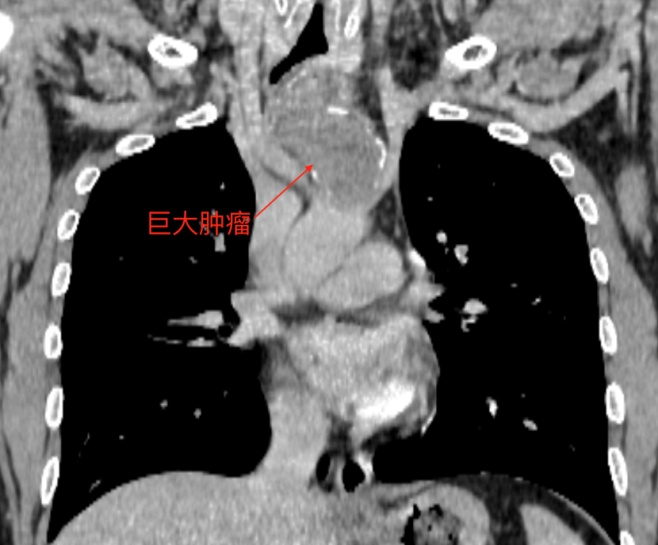

“胸骨肿瘤发病率极低,属于临床上罕见的胸壁肿瘤。”广医三院心胸外科刘盛华主任介绍。从小陈的胸部CT中可见,小陈的胸骨肿瘤就长在胸廓的入口处,位于锁骨间的正下方,靠近心脏、肺等重要器官,而且肿瘤已有10厘米,严重压迫了气管。

20岁的小陈(化名)本应精力旺盛、身体强健,但他最近却连续咳嗽了三个月,始终没有好转。被当做感冒和肺炎治疗多次后效果都不明显,随后转到当地三甲医院检查,才发现病因——小陈的胸骨上竟然长了一个巨大的肿瘤,就位于两个锁骨间的正下方。肿瘤大小已有10厘米左右,相当于一个成年人拳头大小。巨大的肿瘤还压迫了旁边的气管,将气管压扁才导致了小陈咳嗽不断。